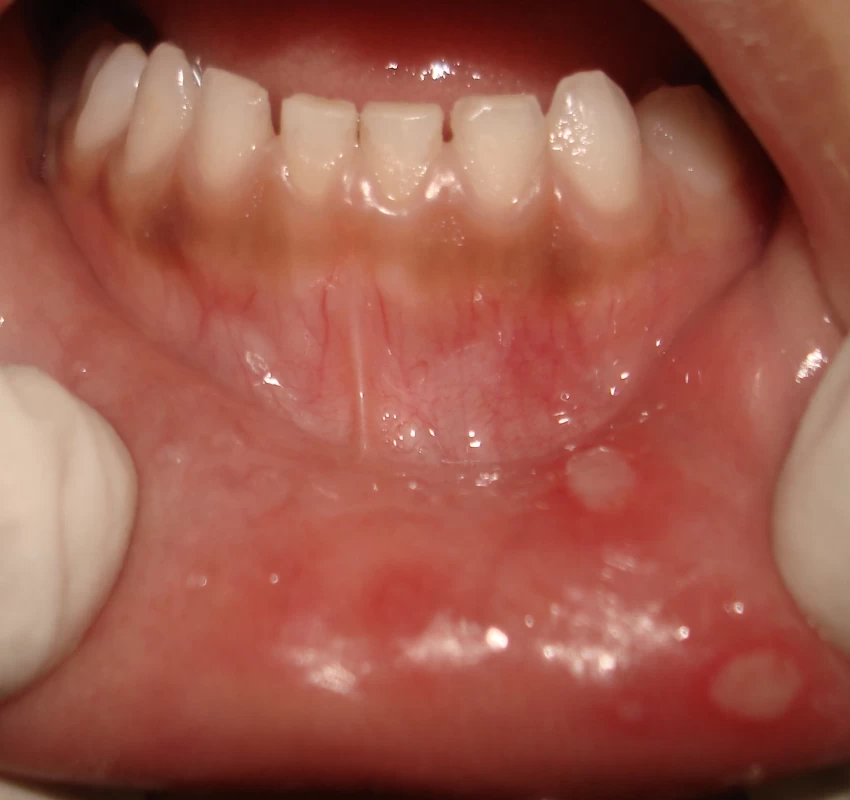

The term LASER is an acronym for 'Light Amplification by the Stimulated Emission of Radiation'. As its first application in Dentistry by Miaman, in 1960, LASER has seen various hard and soft tissue applications. In the last two decades, there has been an explosion of research studies in LASER application. Soft tissue application includes treatment of premalignant lesions and conditions such as leukoplakia, lichen planus, OSMF, treatment of ulcers, excision of traumatic fibromas etc. Besides these, low-level LASER therapy also proved to have biostimulative, regenerative, analgesic, and anti-inflammatory effects on temporomandibular disorders (TMDs) & orofacial pains. Thus, the use of the LASER proved to be an effective tool to increase efficiency, specificity, ease, and cost, and comfort of the dental treatment.